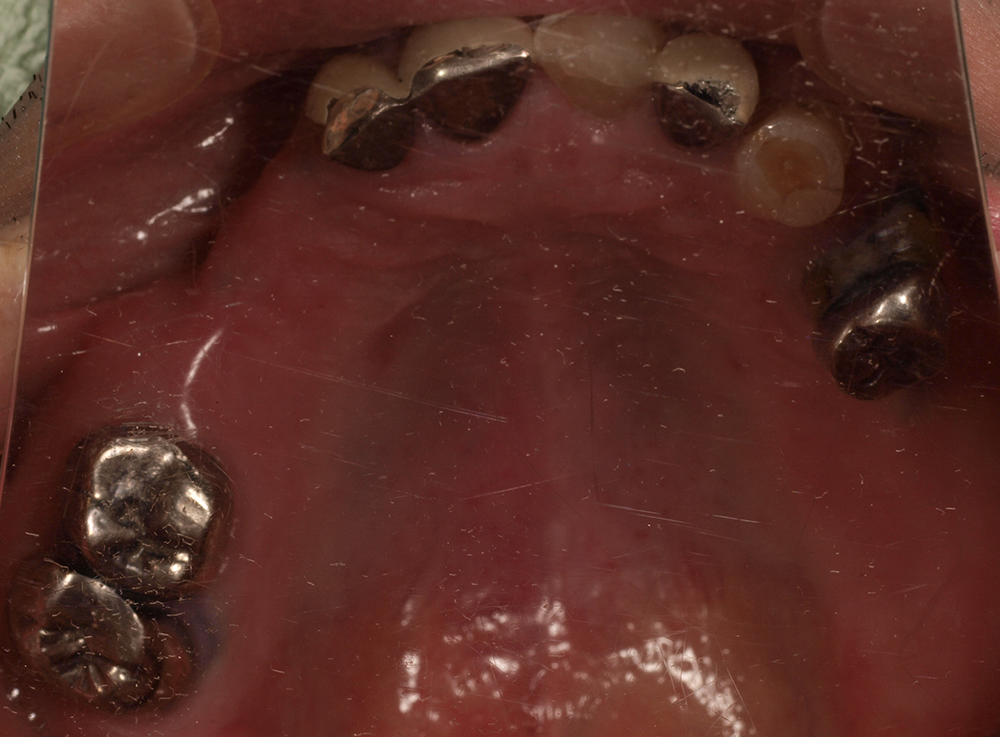

当院では、病気が起こる前の段階からリスクを評価し、原因が細菌によるものか、噛み合わせなどの力によるものかをしっかり見極めます。そのうえで、結果に基づいた適切な予防策や治療方法をご提案しています。

特にインプラント治療では、埋入前に歯周病菌の除去や噛み合わせの調整を行い、インプラント周囲炎(インプラントの歯茎に起こる炎症)のリスクをできる限り減らすことに力を入れています。